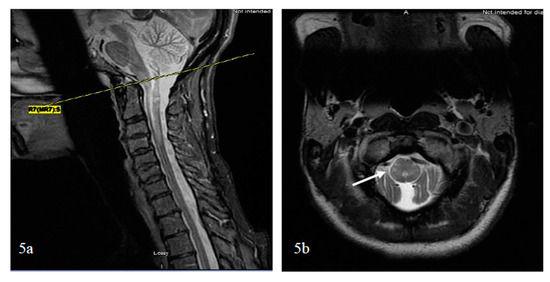

5.2.4. Imaging Patterns of Neuromyelitis Optica Spectrum Disorder-Associated Transverse Myelitis (NMOSD-TM)

Linear Lesions in NMOSD

Bright Spotty Lesions (BSLs) in Neuromyelitis Optica Spectrum Disorder